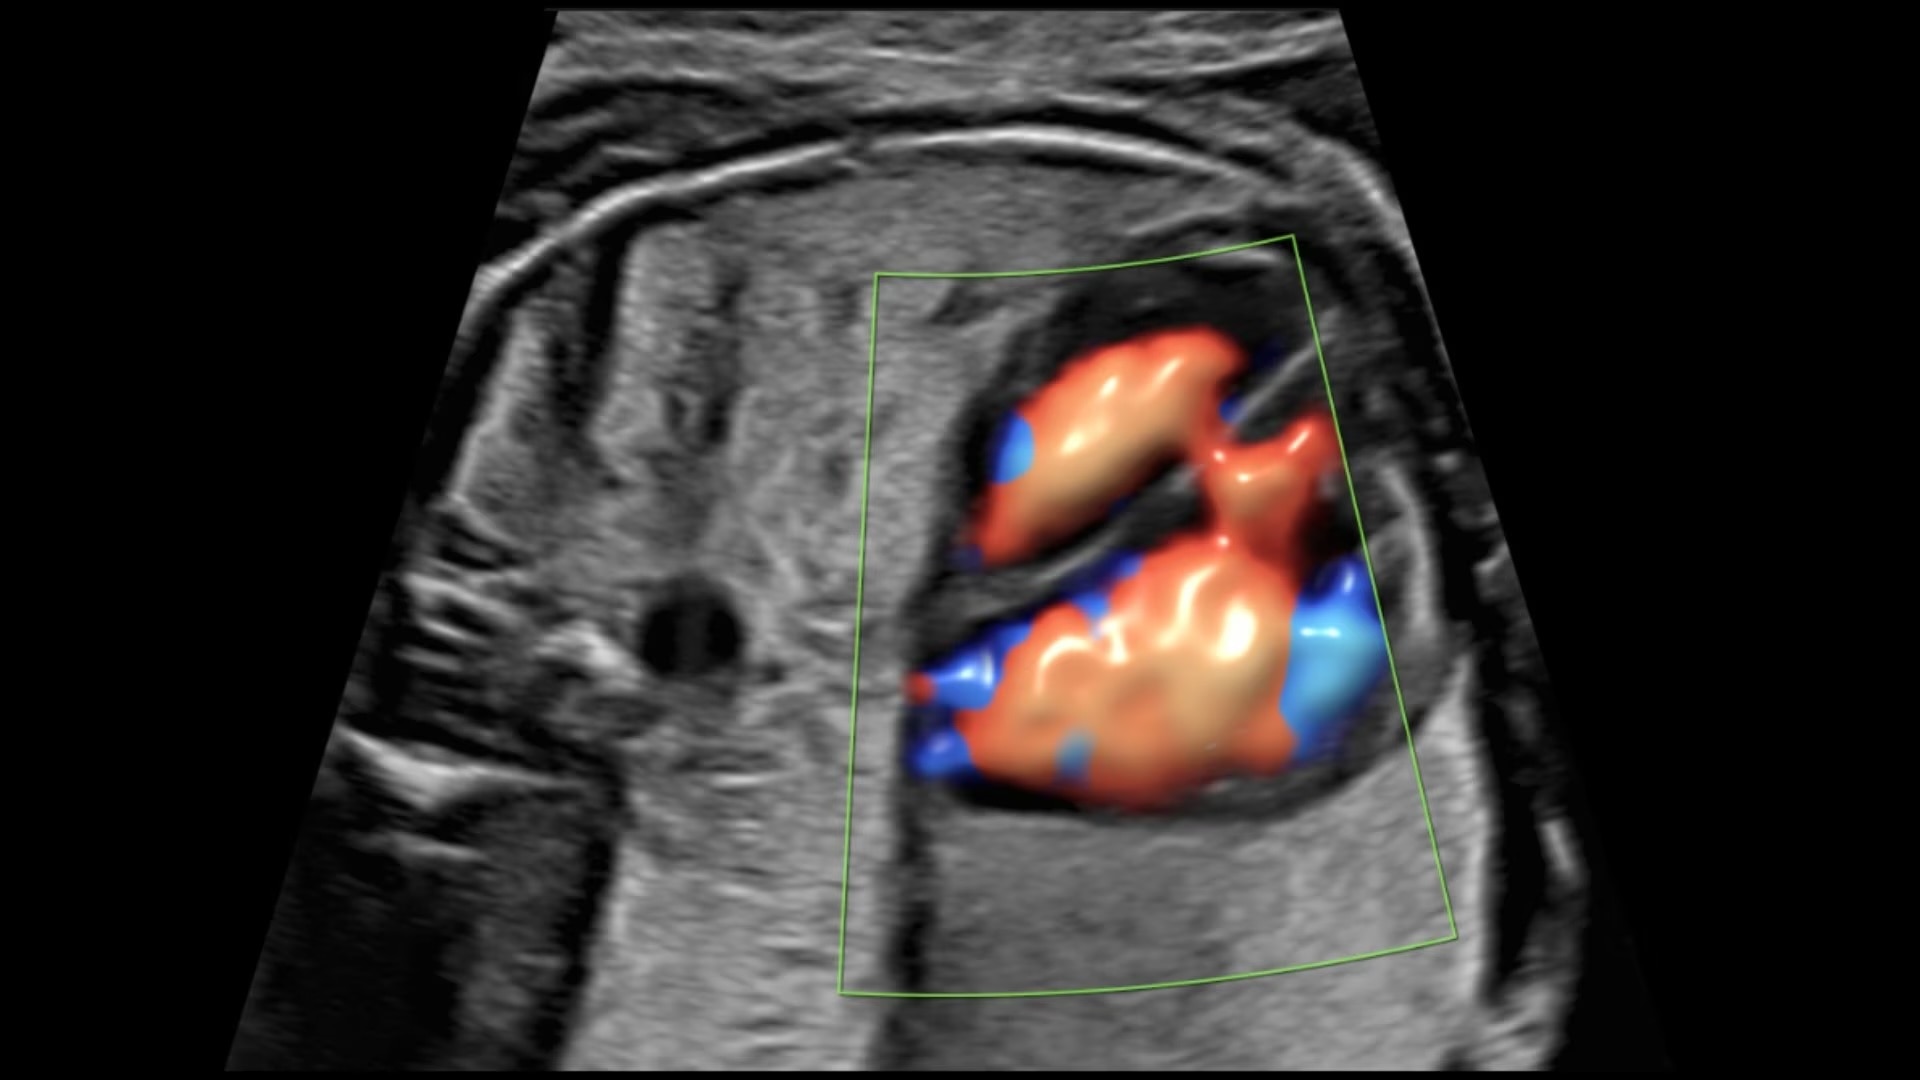

Next level color Doppler for easy, fast visualization of blood flow, displaying a 3D-like appearance.

Uses Color Doppler amplitude to create a 3D-like appearance, helping to clearly separate blood vessels with less flash artifact, improving vessel edge clarity. Available in all color modes, Radiantflow can also be combined with other imaging techniques like spectral Doppler and color M-mode, making it especially useful for visualizing major vessels such as the 3-vessel view (3VV), umbilical cord, arotic arch, and more.